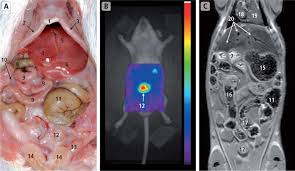

What is a kidney stone? Each kidney stone crystal creates its own unique illness and requires specific treatment. Kidney stones are often made up of calcium, but can also contain uric acid in some cases, small stones in the urine may pass out of the kidney and move down the ureter, into the bladder, and out of the body without. Waste products in the blood can occasionally form crystals that collect inside the kidneys. Owners may notice such signs as vomiting, abdominal pain, food refusal. A majority of kidney stones are calcium stones. Kidney stone disease, also known as nephrolithiasis or urolithiasis, is when a solid piece of material (kidney stone) develops in the urinary tract. If the cat has bladder stones, a stone, or group of stones, will be seen in the urinary bladder, or other parts of the urinary system such as the kidney, ureter, or urethra.10 x research source the merck/merial manual for pet health, <i>urinary stones (uroliths, calcili)'</i>, p.

Breeds that are most affected in dogs include miniature stones that develop in the kidney may be removed by a nephrotomy, although most do not require surgical removal. They won't make any cuts in your skin, but you will be asleep during this procedure. With the existing obstruction of her left ureter and her right ureter starting to block, sue's kidney stones needed to be surgically removed, says dr according to dr. Kidney stones (also called renal calculi, nephrolithiasis or urolithiasis) are hard deposits made of minerals and salts that form inside your kidneys. Ureteral stones are kidney stones that have become stuck in one or both ureters (the tubes that carry urine from the kidneys to the bladder). Get regular urine tests to confirm healthy kidneys. You've probably heard of kidney stones , or you may know someone who's had a kidney stone. (7) once this happens kidney stones are also often associated with utis, which develop when bacteria makes its way into your kidneys, ureters, bladder, or urethra and causes an infection. Pain in the back and side, often just below the ribs. Not sure what a ureter stone is? Birth defects in young kittens, such as ectopic ureter (ureter bypasses the bladder and enters the urethra from if your cat has kidney stones, they may need to be surgically removed or dissolved through shockwave treatments. The prevalence of kidney stones in the united states. I went to the er doubled over in pain, nausea and vomiting.

Problems occur when stones pass from the kidney into the ureter and form a partial or full blockage. Ureteral stones are kidney stones that have become stuck in one or both ureters (the tubes that carry urine from the kidneys to the bladder). Many cats with kidney stones have no apparent signs; Stones from the kidney or ureters of cats have been diagnosed as calcium oxalate in 70% of cases. Kidney stones are stones formed from minerals that lodge in the kidneys. I went to the er doubled over in pain, nausea and vomiting. Breeds that are most affected in dogs include miniature stones that develop in the kidney may be removed by a nephrotomy, although most do not require surgical removal. What is a kidney stone?